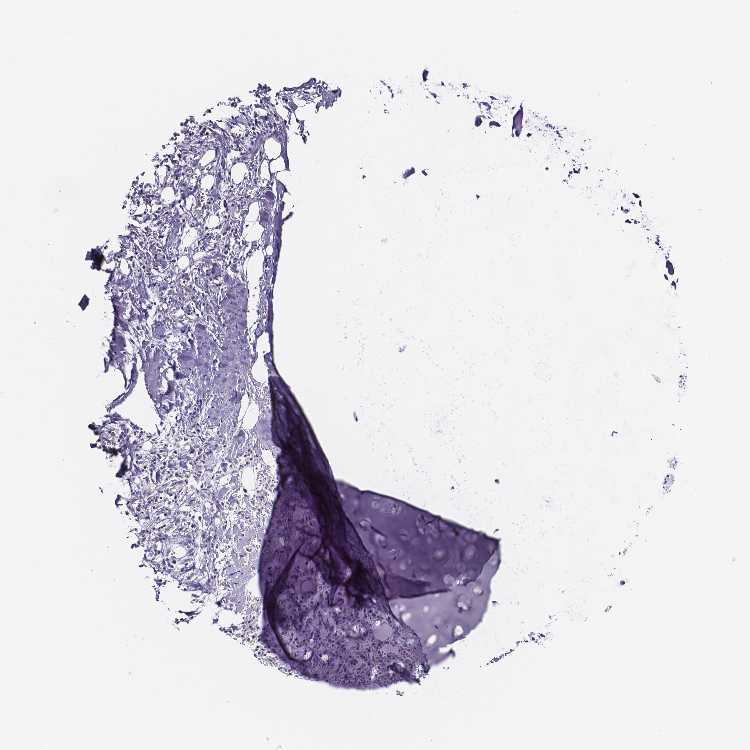

SOFT TISSUE 1 - Antibody stainingi

Antibody staining in the annotated cell types in the current human tissue is reported as not detected, low, medium, or high, based on conventional immunohistochemistry profiling in selected tissues. This score is based on the combination of the staining intensity and fraction of stained cells.

Each image is clickable and will lead to virtual microscopy that enables deeper exploration of all samples and also displays staining intensity scores, fraction scores and subcellular localization as well as patient and tissue information for each sample.

Antibody HPA038104

Chondrocytes Not detected

Fibroblasts Not detected

SOFT TISSUE 2 - Antibody stainingi

Peripheral nerve Not detected